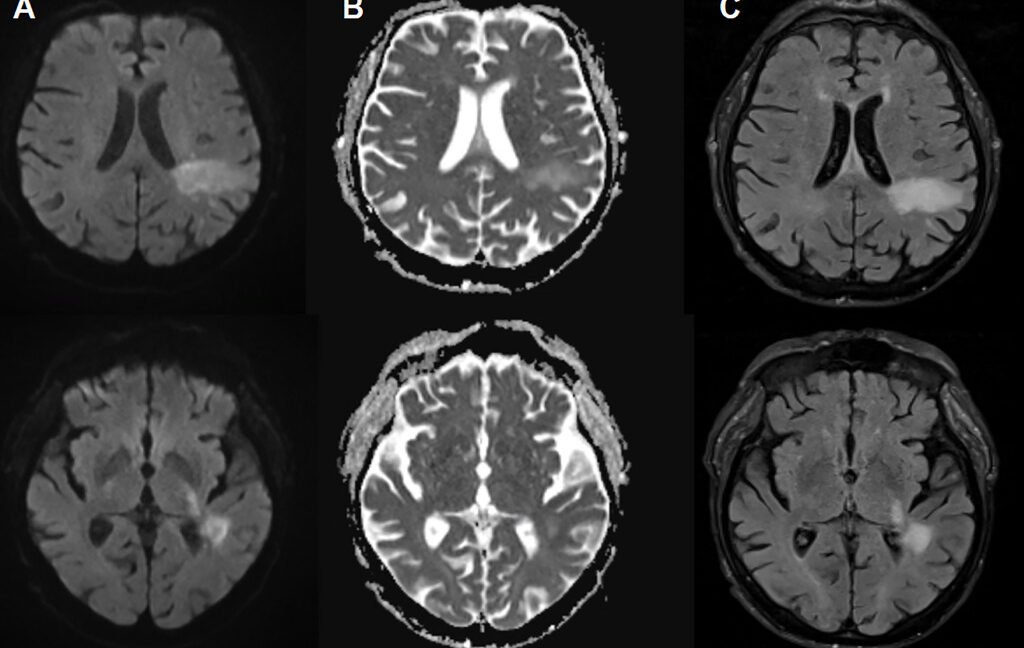

In PML, the brand new disease-causing virus or “PML-type” JC virus actively invades the mind, blowing up particular mind cells, together with the cells that type the insulating myelin sheaths that shield nerve cells. This results in intensive demyelination, which ends up in nerve cell dysfunction and demise. On imaging, PML can present up as signature lesions within the mind. These imaged lesions, paired with check findings of JC virus DNA in cerebrospinal fluid, are how PML is identified. However for sufferers experiencing PML, the signs can mimic all the things from a stroke to a number of sclerosis, inflicting issues like speech impairments, visible defects, motor dysfunction, and seizures.